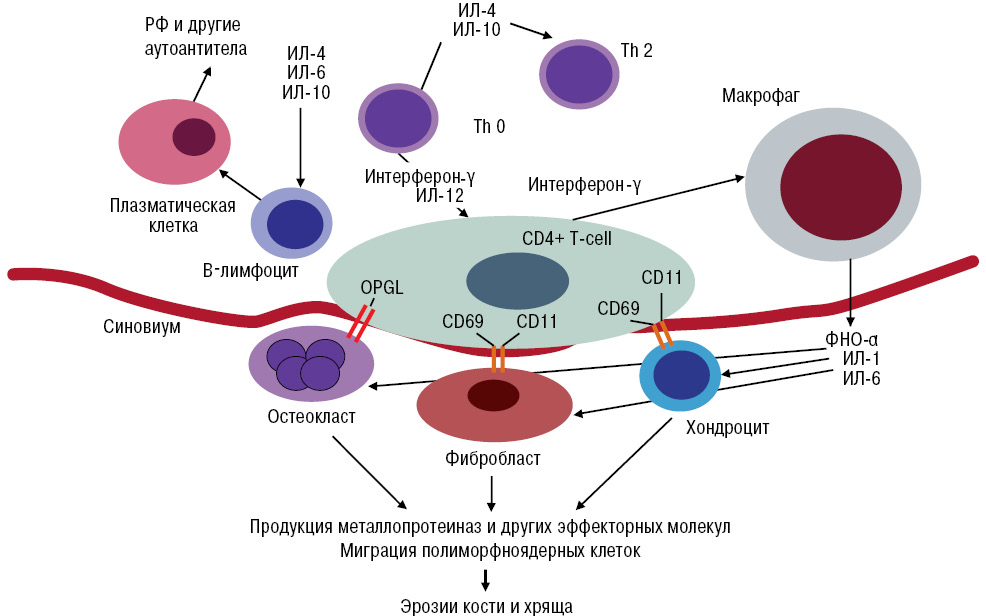

Механизмы действия антимикотиков: схемы и изображения